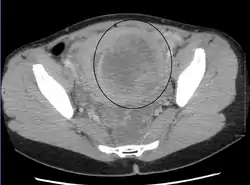

الفحص باليدين قادر على تحديد وجود الأورام كبيرة الحجم، يعد استخدام الموجات فوق الصوتية أداة التشخيص المثالية لتقدير وجود الورم. يصف التخطيط بالموجات الصوتية الورم على أنه كتل بؤرية غير متجانسة النسيج، والتي تؤدي إلى تظليل في الإشعاعات فوق الصوتية، ويمكن تحديد موقع وأبعاد الورم، كما يمكن استعمال التصوير بالرنين المغناطيسي لوصف الورم وأبعاده وموقعه في الرحم. طرق التصوير لا يمكنها التمييز بدقة بين الورم الخبيث والحميد، على الرغم من أن الورم الخبيث يعد نادرا. النمو السريع أو المفاجئ بعد انقطاع الطمث سوف يزيد الشك من وجود ورم خبيث في الرحم، وقد يكون هناك آثار غزو للأنسجة المحيطة. نادرا ما يتم أخذ خزعة للتشخيص، وإذا تم أخذها، فإنها لا تكون تشخيصية، واذا لم يكن هنالك تشخيص واضح بعد التصوير، يتم الإيعاز بالجراحة . ومن طرق التصوير الأخرى التي لها أهمية في تقييم الورم الذي يؤثر على التجويف الرحمي: تصوير الرحم وقنوات فالوب، والتصوير بالموجات الصوتية بعد ملئ الرحم بسائل .

ورم ليفي عضلي كبير الحجم (9 سم )، والذي يسبب متلازمة احتقان الحوض كما يظهر في صورة محورية.